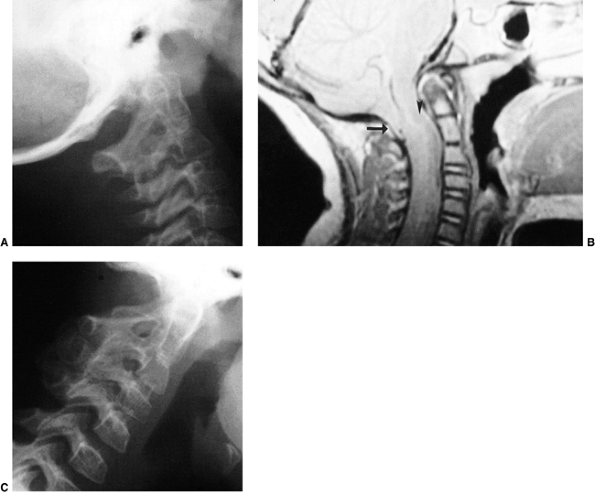

Figure 22.8

This girl, 3 years and 9 months of age, had a history of vertex headaches for 1 year. One month prior to presentation, she developed a painful, left-sided torticollis. A: Plain lateral radiograph shows fusion of C2 and C3 and absence of the ring of C1 with occipitalization. B: Magnetic resonance image (MRI) shows an Arnold-Chiari malformation, with herniation of the cerebellar tonsils into the foramen magnum (arrow). Also note the cordal edema (arrowhead). C: The child underwent an occipital decompression and laminectomy to C3, posterior cervical fusion from the occiput to C4, and halo cast immobilization for 4 months. Flexion and extension lateral radiographs 1 year after treatment show solid incorporation of the fusion from C2 to C4, with dissolution of the graft from the occiput to C2. However, there is no atlantooccipital instability. The child’s symptoms resolved. |

atlantooccipital junction present with a wide spectrum of deformities.

In these patients, the anterior arch of C1 is commonly assimilated to

the occiput, usually in association with a hypoplastic ring posteriorly

(Fig. 22.8) as well as condylar hypoplasia. The

height of C1 is variably decreased, allowing the odontoid to project

upward into the foramen magnum (i.e., primary basilar impression). More

distal cervical anomalies can also occur in association with the

atlantooccipital anomaly. The odontoid may be misshapen, or directed

more posteriorly than normal. Up to 70% of children with this condition

have a congenital fusion of C2 and C3 (Fig. 22.8).